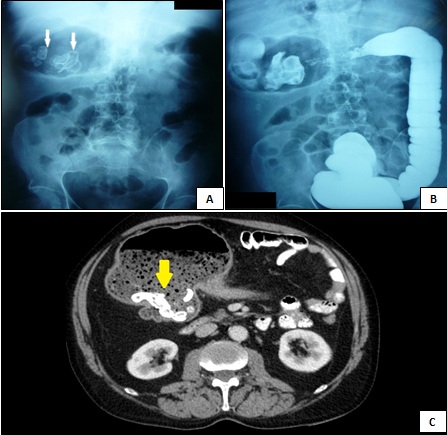

Presentamos el caso de un varón de 61 años con antecedentes de enfermedad de crohn que de forma incidental, en la radiografía simple de abdomen, se observa una gran imagen redondeada con múltiples imágenes radiopacas en su interior a nivel de hipocondrio derecho.

La tomografía abdominal mostró una zona de estenosis en colon transverso y a nivel de hipocondrio derecho una zona preestenótica, dilatada, con material fecaloideo en su interior con múltiples imágenes hiperdensas compatible con fecalitos.